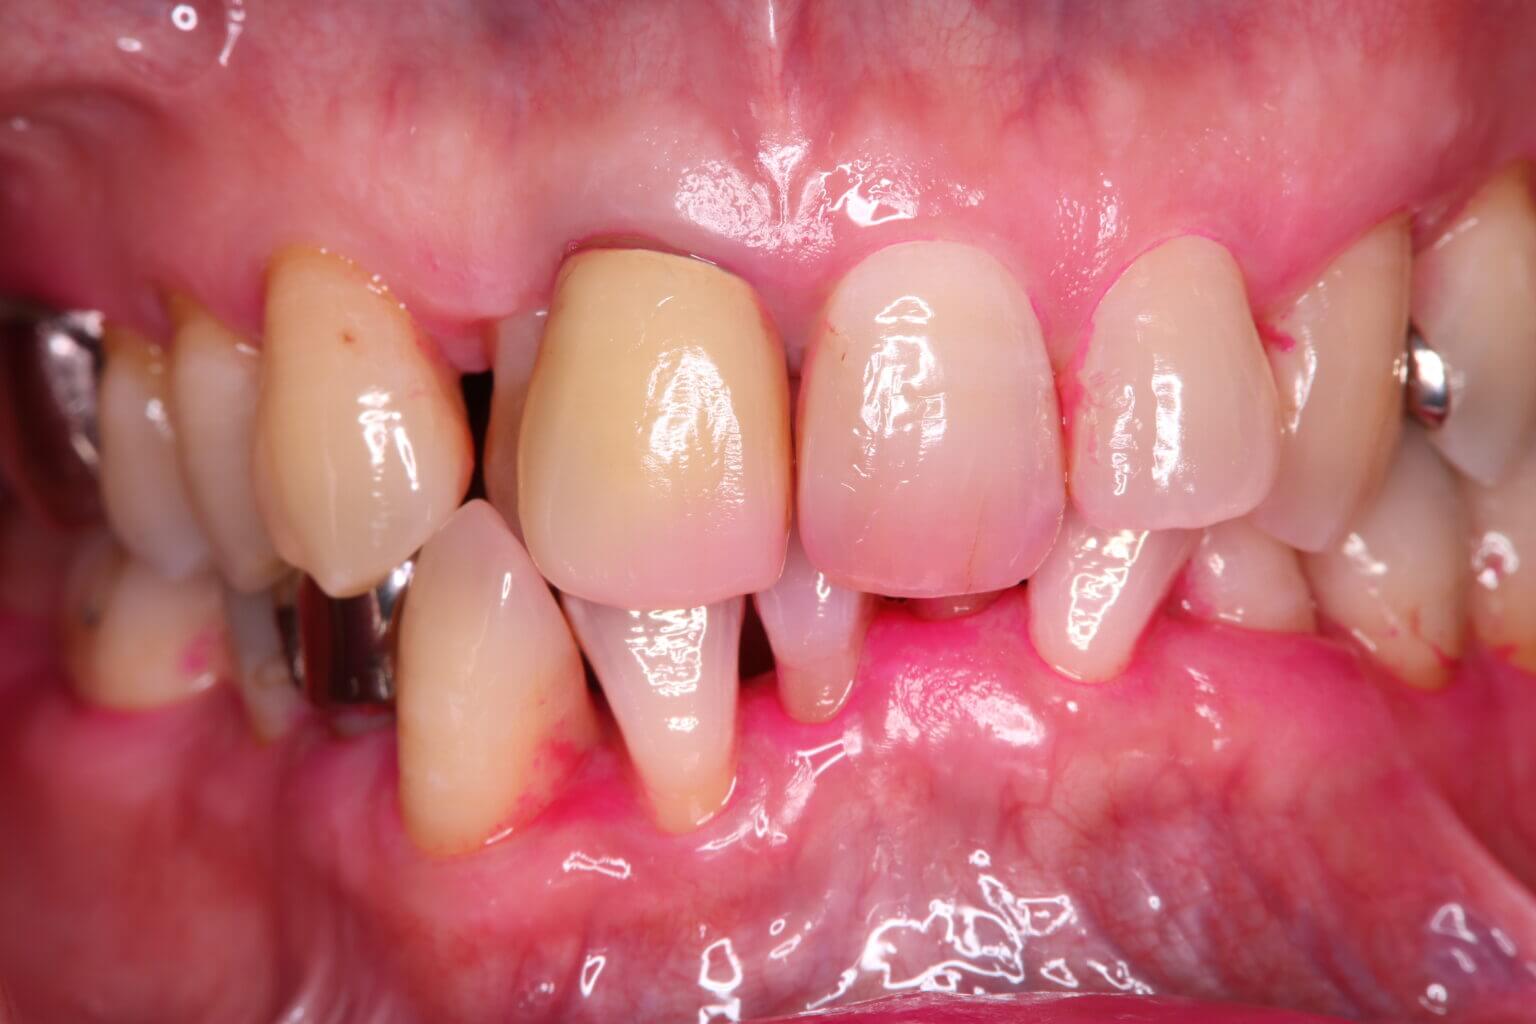

④口の中の写真

この検査は、治療の進行状況や口腔内の状態を詳しく記録するために非常に役立ちます。写真は治療の検査でとても重要です。治療を始める前に、歯や歯ぐきの状態を写真に記録することにより、治療の効果を比較することができます。そして、写真をもとに、どの部分に重点的な治療が必要かを確認し、最適な治療計画を立てます。そして定期的に写真を撮ることで、治療の効果や進行状況を確認し、必要に応じて治療計画を調整します。